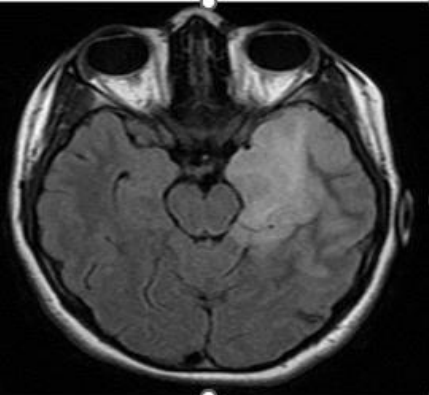

Figure 1: 17-year-old female patient with anti-NMDAr encephalitis (seropositive). Cerebral MRI, FLAIR sequence: left temporo-insular hyper signal.

Brain MRI often objectified parenchymal abnormalities (86.7% of cases), which were similar to those reported in the literature [25, 51], including isolated temporal lesions (36.6% of cases). They were more bilateral than unilateral. Extra limbic radiological abnormalities were found in half of the cases. The most affected localisations are mainly the frontal lobe, the basal ganglia, and rarely other structures, such as the insula, parietal lobe, occipital lobe, meninges and white matter are affected. These extra limbic anomalies have been reported in the literature at a lower frequency than ours (40% of cases) [51]. Graus et al. included bilateral temporal involvement (in T2 and FLAIR) in the criteria for defined autoimmune encephalitis [23]. Unilateral temporal impairment would be possible. However, in this case, Graus et al. required the presence of antibodies to classify it as autoimmune encephalitis because other etiologies, such as glioma, seizures, and HSV1, could cause a unilateral temporal hyper signal [23].